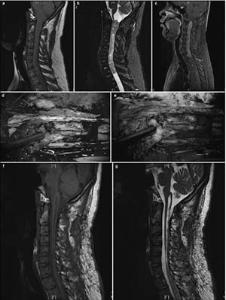

20171023161526 Figure 1 Pre- and postoperative magnetic resonance imaging of intramedullary ependymomas at C1–T1, and intraoperative observations. (a) Preoperative sagittal T1 image reveals spinal cord thickening. (b) T2 image shows high intramedullary signal intensity at C1–T1, but no signal at either end. (c) Enhanced scanning reveals distinctive tumor enhancement. (d) Intact tumor with clear boundaries, as viewed under a microscope. (e) Tumor images, viewed via fluorescence microscopy, showing a distinctive basal structure. Sagittal T1 (f) and T2 (g) images, 3 months after surgery, do not show tumor residuals or relapses.